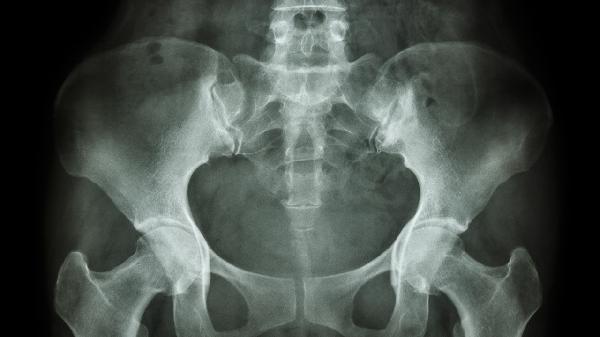

髋关节是连接股骨与骨盆的球窝关节,负责下肢活动;骨盆是由髋骨、骶骨和尾骨组成的环形骨性结构,承担支撑躯干和保护盆腔器官的功能。

1、解剖位置

髋关节位于骨盆两侧的髋臼与股骨头之间,骨盆则构成躯干基底,上接脊柱下连下肢。

2、结构组成

髋关节由股骨头、髋臼及关节囊构成,骨盆由左右髋骨、骶骨及韧带共同连接形成骨环。

3、功能差异

髋关节主导屈伸旋转等运动功能,骨盆主要起支撑重量、保护内脏及分娩通道作用。

4、关联病症

髋关节易发骨关节炎和股骨头坏死,骨盆常见骨折和骶髂关节紊乱,两者可能相互影响。